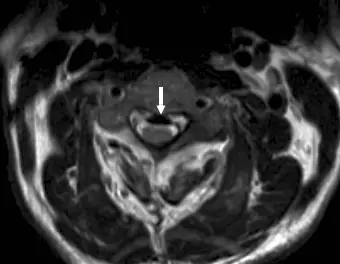

71 歲男性不慎跌倒之後,頸部異常疼痛,合併有上肢酸麻感覺;磁振掃描橫向 T2 加權影像如附圖。其最可能的診斷為何?

本題考查頸椎後縱韌帶骨化症(ossification of the posterior longitudinal ligament, OPLL)的 MRI 影像特徵與臨床表現。71歲男性跌倒後頸部疼痛合併上肢酸麻,MRI T2 加權橫切面影像顯示特定影像所見,需判斷最可能的診斷。

本題提供頸椎 MRI 橫向(軸位)T2 加權影像,白色箭頭指向椎管前方一個明顯的低信號(hypointense)帶狀或塊狀結構,緊貼脊椎椎體後緣,位於硬脊膜(dural sac)前方。

- 低信號區域:在 T2 加權影像上呈現低信號強度,此特徵提示骨化(ossification)或礦化組織,因骨皮質(cortical bone)和緻密礦化組織在 T2 影像上均呈現低信號

- 位置:緊貼椎體後緣,沿後縱韌帶走行區域,符合後縱韌帶骨化(OPLL)的典型解剖位置

- 椎管狹窄:低信號區域佔據部分椎管空間,壓迫硬脊膜囊,造成有效椎管管徑縮小

- 脊髓壓迫:白色箭頭所指的低信號結構由前方壓迫脊髓(spinal cord),脊髓可能出現形態改變

此影像表現最符合 後縱韌帶骨化症(OPLL):韌帶組織被異常骨化,在 T2 影像形成典型的低信號帶,位於椎體後方/椎管前壁,造成椎管狹窄及脊髓壓迫